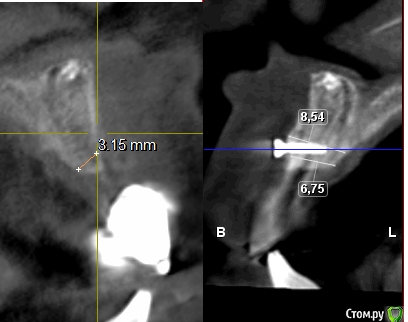

Евгений Ходыкин Опубликовано 8 июля, 2016 Поделиться Опубликовано 8 июля, 2016 Коллеги, что за образование? Сосуд? Как быть с постановкой имплантата?http://s12.radikal.ru/i185/1607/ba/b87b9616d8b7.jpg Ссылка на комментарий

Доктор Добрых Дел Опубликовано 8 июля, 2016 Поделиться Опубликовано 8 июля, 2016 Есть одна пациентка у неё вся в/ч в переднем отделе в таких "образованиях" прич м если проследить их ход то идут либо в пазуху либо к латеральной сленке пазухи либо в полость носа. Тоже ломал голову что это - сосудов таких больших не должно быть вроде.. Но там имплантация не планировалась так что просверлить "это" не доводилось ) Ссылка на комментарий

Рузанов Алексей Опубликовано 10 июля, 2016 Поделиться Опубликовано 10 июля, 2016 Было что-то подобное, рядом с резцовым отверстием. Думал либо ответвление нерва, либо сосуд. Когда сверлился ожидал кровотечение, но ничего не произошло, ровным счетом как и с чувствительностью. Ссылка на комментарий